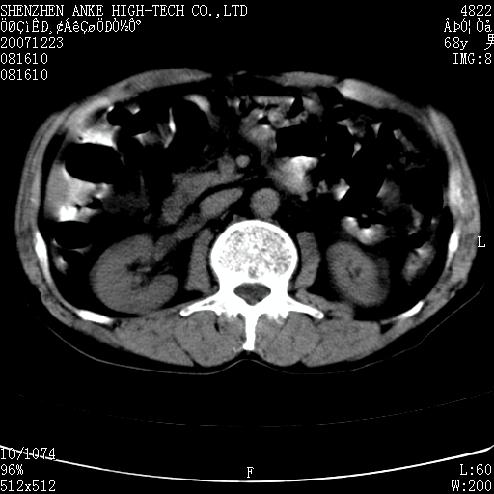

患者:男,63岁,2年前胆囊切除术后,现右上腹部剧烈疼痛近2天.

有无外伤史?右肾包膜下血肿可疑。

主要是问右肾有没有问题?患者无明显外伤史.

未见异常,病人差闭气,伪影较多.

肠管积气明显.

肠道准备不好,干扰影大。

肠道气体伪影干扰太大了,应该是干扰所致,未见明显异常。

肠道准备不好,胃底后壁显示不清,右肾改变考虑为伪影。

上腹部ct平扫未见明显异常。(肠道气体较多,患者呼吸了)

请看第一张正位片,胸主动脉象有扩张,胸主动脉瘤?